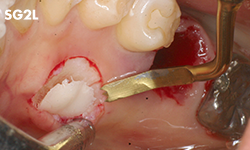

Eliminación de tejido de granulación de la zona de extracción.